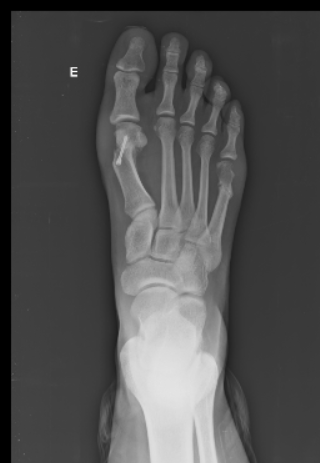

Exames de imagem, como radiografia, podem ser solicitados para avaliar o grau da deformidade e auxiliar na escolha do tratamento e definição de técnica cirúrgica. É importante ainda obter dados sobre as condições de saúde do paciente, tais como doenças reumatológicas, neurológicas e vasculares, diabetes, infecções fúngicas nos pés, alterações degenerativas de outras articulações e alinhamento do retropé.